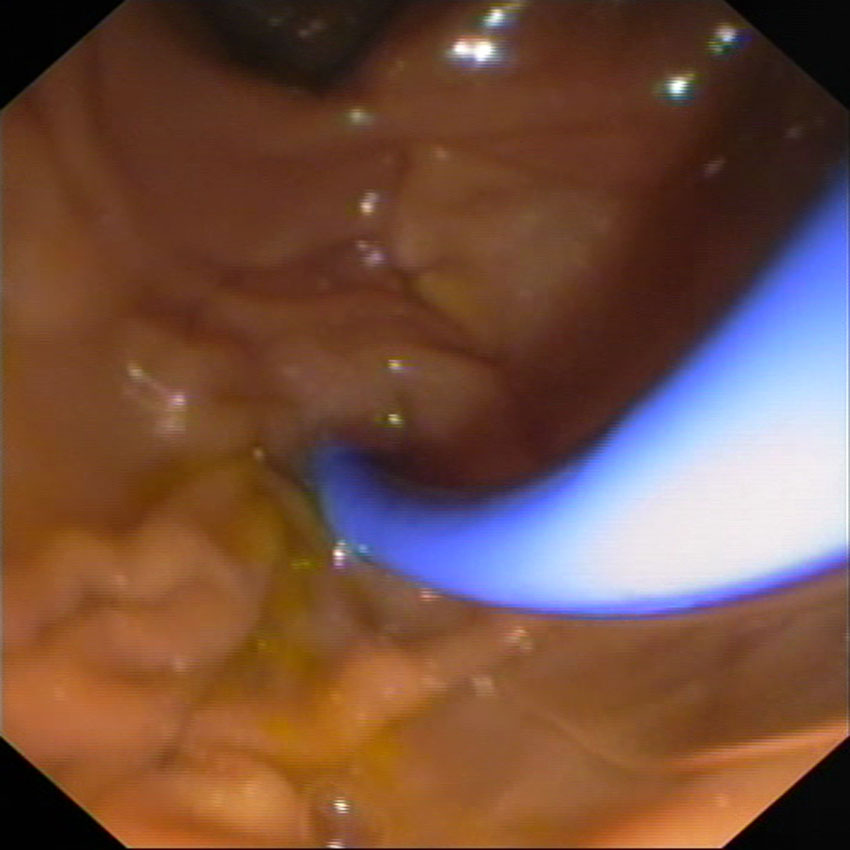

Varón de 78 años de edad ingresado en el Servicio de Cirugía General por

colelitiasis y colédocolitiasis con evolución tórpida. Dicho Servicio y la UCI solicitan nuestra

valoración el 4 de junio por presentar un shock séptico de origen biliar. Decidimos

realizar CPRE urgente, planificando el drenaje la vía biliar sin esfinterotomía

por la coagulopatía que presentaba. Se lleva a cabo una canulación biliar

estándar y una colangiografia que muestra la existencia de dos colédocolitiasis,

completando la exploración a continuación mediante la inserción de una prótesis

plástica 8.5F.